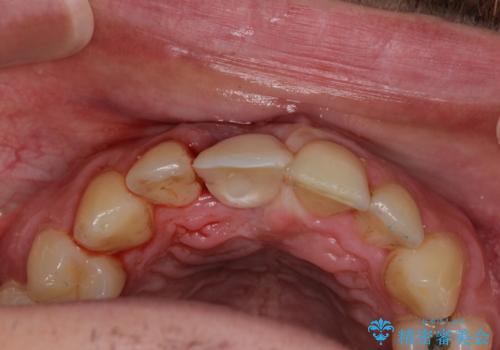

磨き残しなどによるプラークの付着が多いため、仮歯の用意と手術アポイントの調整を行っている間に口腔内のクリーニングなどを施し、環境がある程度改善されたのちに、抜歯即時インプラント埋入、即時荷重(インプラント埋入時に仮歯の装着)の予定で治療を行うこととしました。

度重なる脱離により、表側の炎症が非常に強くなっており、歯を支える骨が失われている状態でした。

そのため、現在の位置よりも歯と歯肉の位置が退縮する方向に移動する可能性があり、前歯2本の歯肉位置が大きくずれることとなるため、本人との相談のうえ、天然歯が萌えているような歯肉状態とはならないものの、2本の段差が少ない状態にて治療を終えることとなりました。